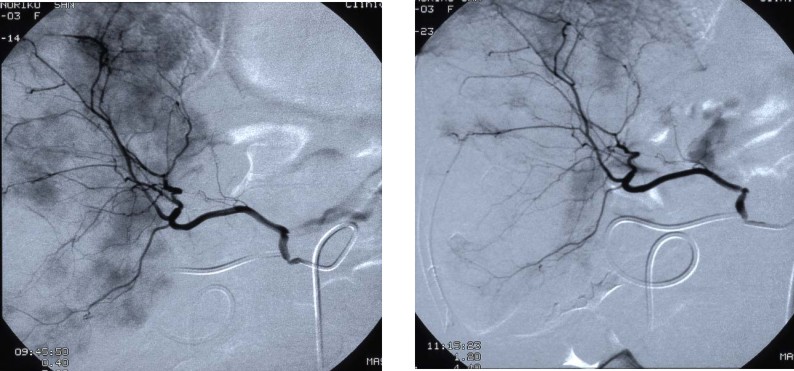

介入放射学

肿瘤微血管介入示意图

介入放射学是在医学影像设备的引导下,利用导管、导丝等器材对各种疾病进行诊断和治疗的学科。人体有很多固有的管道,如大血管、食管或气管-支气管等,如果这些管道或其临近的组织器官出了问题,按照传统的方法,我们需要求助于外科来开刀治疗,这样给患者带来的创伤很大。而介入治疗则是充分利用了人体的固有管道来进行治疗,简单地说就是利用专门的器械通过人体固有的管道上,在人体内部进行操作,不用开刀,创作小,恢复快。